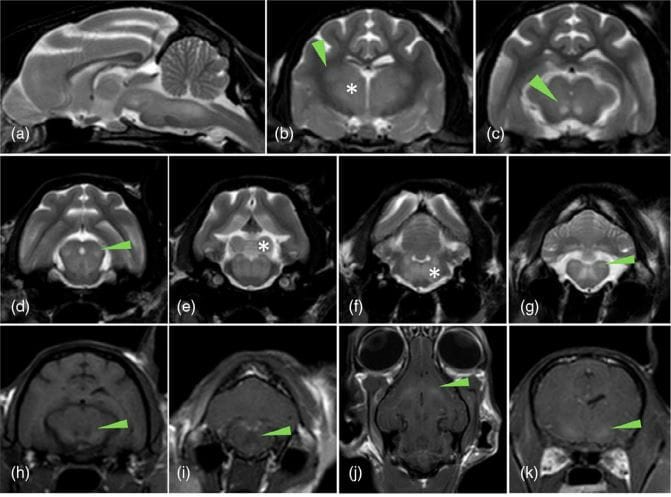

Magnetic resonance imaging of a cat with hepatic encephalopathy due to congenital extrahepatic portosystemic shunts revealed bilateral symmetrical T2-weighted (T2W) hyperintense and T1-weighted (T1W) hypointense non-contrast-enhancing lesions in the thalamus, lateral geniculate nuclei, red nuclei, caudal colliculi, vestibular nuclei, olivary nuclei and dentate nuclei, and T1W hyperintensity in the lentiform nuclei. (a) Sagittal T2W sequence showing diffuse T2W hyperintensity in the brainstem. Transverse T2W sequences showing bilateral symmetric T2W hyperintensities in the (b) thalami (asterisk) and lateral geniculate nuclei (arrowhead), (c) red nuclei (arrowhead), (d) rostral colliculi (arrowhead), (e) caudal colliculi (asterisk) and reticular formation, (f) white matter (asterisk) and (g) vestibular nuclei (arrowhead). Transverse (h and i), dorsal (j) and transverse (k) T1W precontrast sequences showing T1W bilateral hypointensity of the red nuclei (arrowhead; h), white matter (arrowhead; i) and T1W hyperintensity of the lentiform nuclei (arrowhead; k and l).